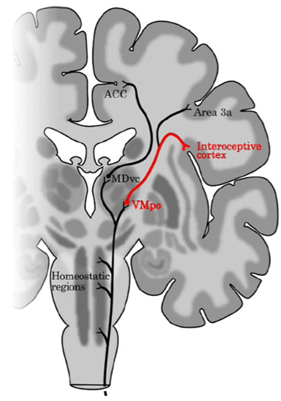

Beskriv övergripande banan för interoception upp till och med interoceptiva kortex och limbiska motorkortex

Thalamokortikala förbindelser

Beskriv dessa olika typer av förbindelser och vad det är viktiga för gällande interoception

Förklara interoceptionens lateralisering, utgå från lamina 1